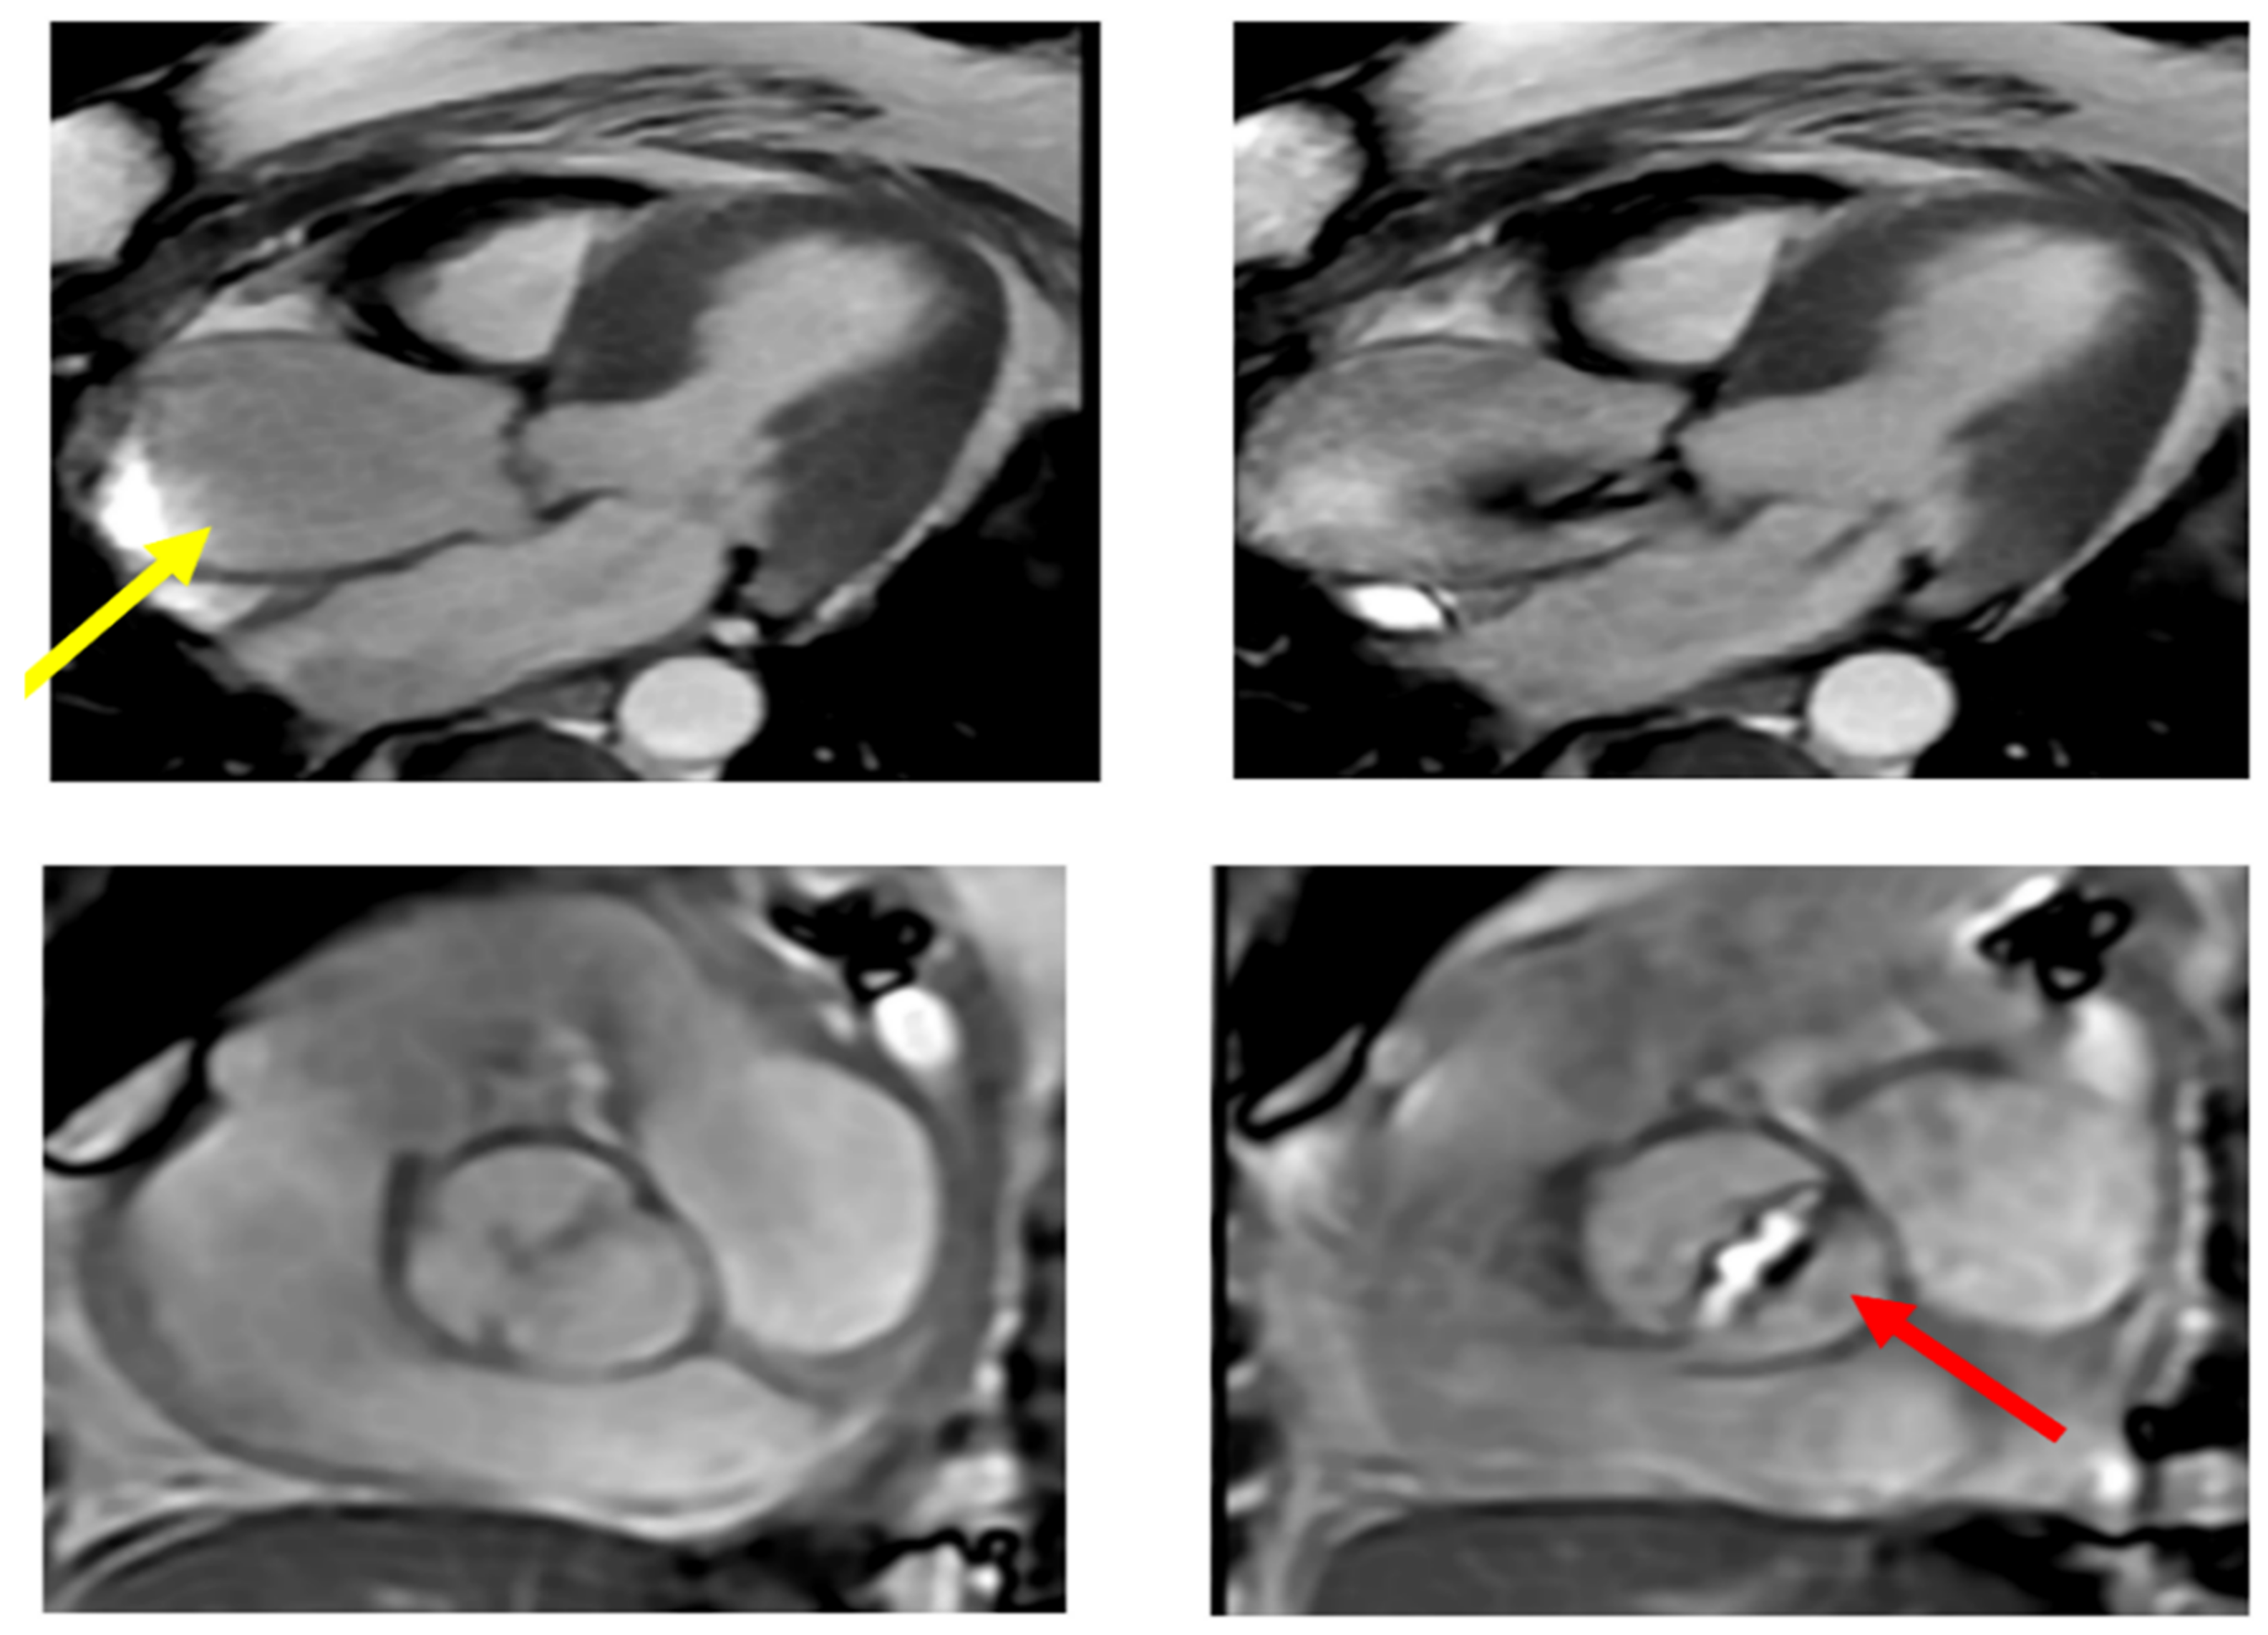

The contribution of the MR is relevant in those cases in which the echocardiography cannot estimate the morphology of the aortic valve and root and the diameter of ascending aorta and arch (Figure 9). It also has a complementary role in determining the aortic wall structure and the viability of myocardial muscle. It has a main role in determining scarry zones inside a healthy myocardium and the efficiency of cardiac chambers. EF may be estimate with this technique. These features should be matched with other decision elements derived from other imaging techniques to identify the proper surgical indication and forecast the patients’ prognosis. These factors make MR more useful in clinical practice than CT scan regarding functional evaluation [98] (Figure 9).

Figure 9.

Calcific bicuspid aorta Sievert Type 2 with fusion of the two coronary cusps for a raphe (red arrow). The patient had a transvalvular gradient of 40 mmHg. The ascending thoracic aorta is dilated above the Valsalva sinuses with a maximum diameter of 53 mm measured at the intersection with the right pulmonary artery (yellow arrow).